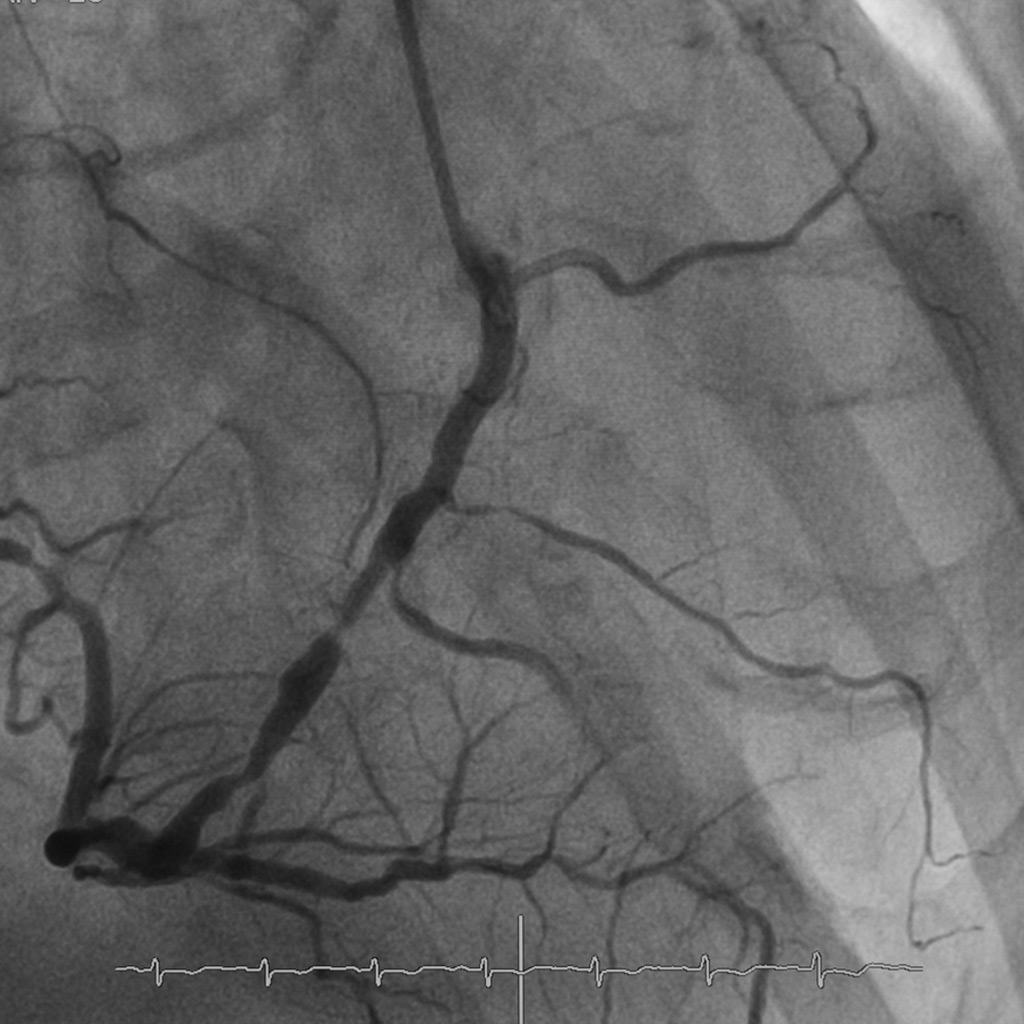

Coronary angiography is a diagnostic procedure that permits cardiologists to picture the blood vessels providing the heart. It includes the utilization of a different dye and X-ray imaging to look at the coronary arteries for blockages or irregularities.

2. Evaluation of Blood Flow to the Heart: During a coronary angiogram, the flow of blood to the heart can be evaluated. The procedure decides whether there are any areas of reduced blood flow due to blockages or different issues. This data is essential in surveying the seriousness of the condition and guiding further treatment decisions, like the need for angioplasty, stenting, or bypass surgery.

3. Guidance for Interventional Procedures: Coronary angiography also assists as a guide for interventional procedures. If blockages or narrowed arteries are identified, cardiologists can perform angioplasty and stenting during a comparative procedure to restore blood flow. The ongoing pictures obtained through the angiogram aid in accurately setting the stent and guaranteeing its adequacy in opening the blocked artery.